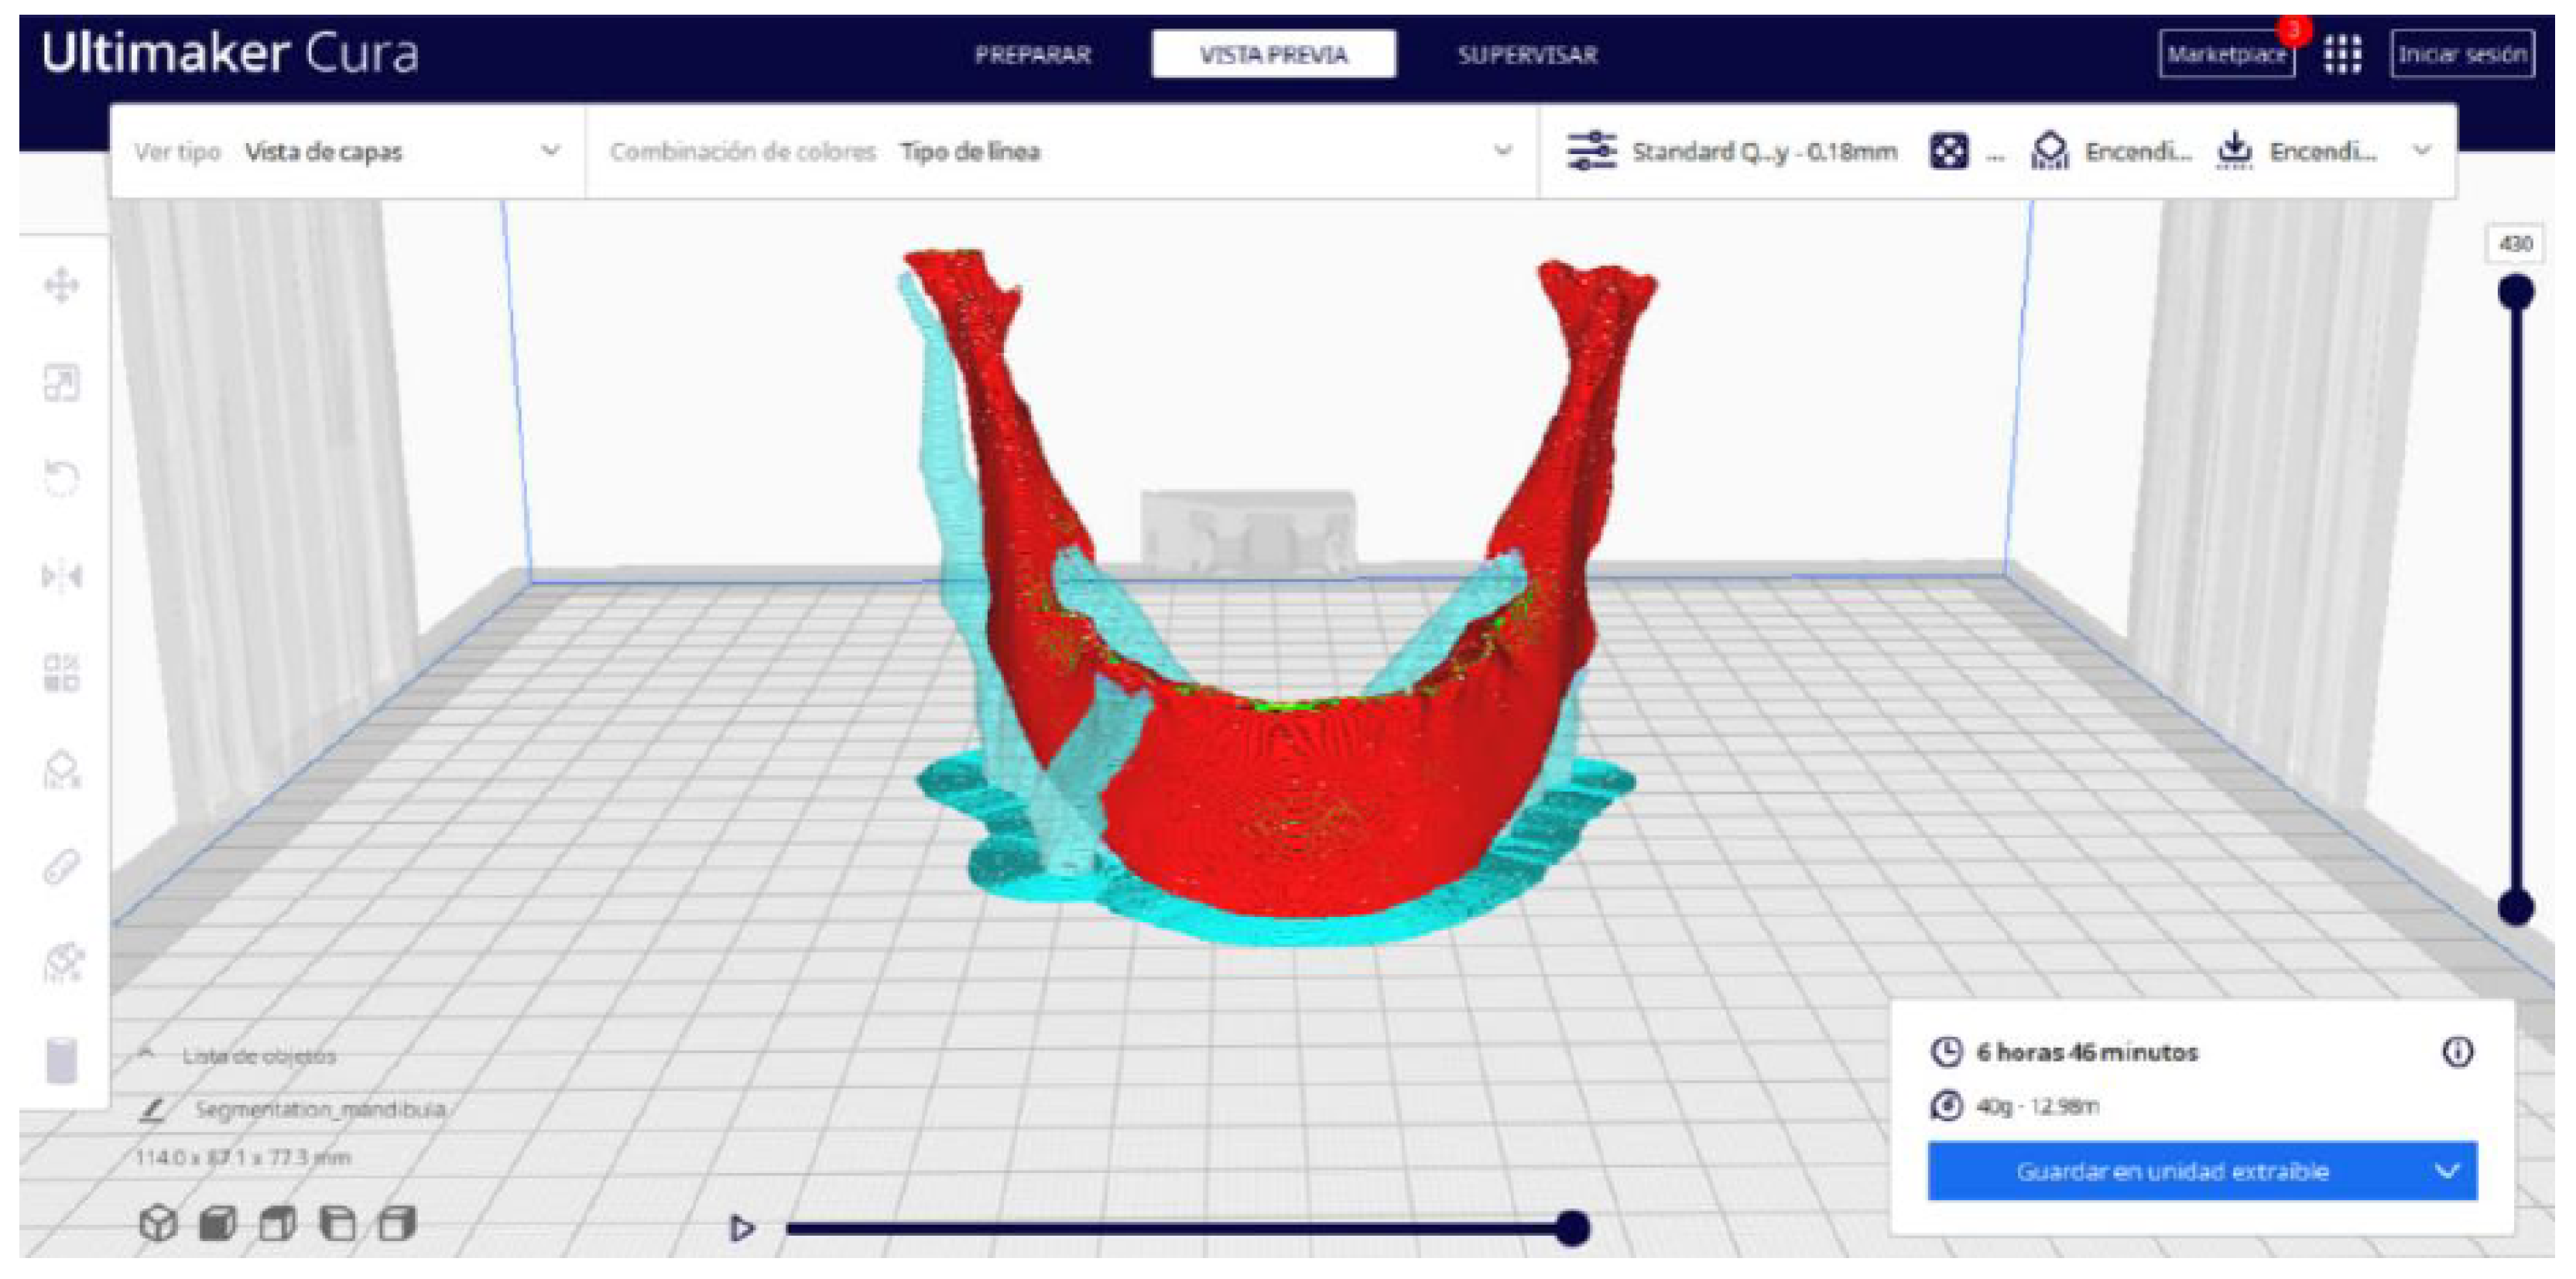

2.2. STL-to-GCODE File Conversion

- Choose the appropriate support structure type and pattern to ensure the successful printing of complex geometries, adjusting the adhesion to the build plate as necessary.

- In order to continue the STL file to GCODE conversion process, select the “Segmentation” option in Ultimaker Cura.

- The segmentation tool provides valuable information such as the estimated model weight and estimated printing time, among other crucial data.

- Once the segmentation is complete, go to the “Preview” option. Here, a sidebar will appear on the right side of the screen, giving you the ability to preview the materialisation process layer by layer, from the base to the top of the model.

3.2. Human Lower Jaw

3.2.2. STL-to-GCODE Files